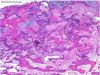

What is this lesion?

Chondrosarcoma The gross image shows a destructive cartilaginous lesion